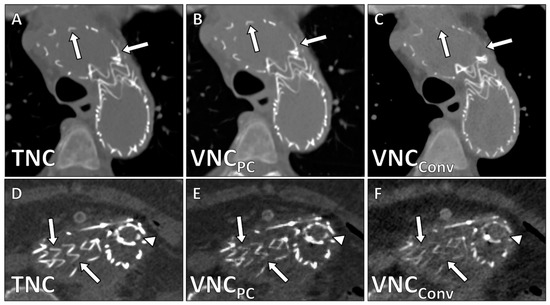

| Image Quality | 4.2 ± 0.9 | 0.68 (0.44–0.78) | 2.5 ± 0.6 | 0.62 (0.43–0.77) | <0.001 |

| Calcium Subtraction | 4.6 ± 0.5 | 0.75 (0.66–0.82) | 3.0 ± 0.6 | 0.58 (0.40–0.71) | <0.001 |

| Stent Subtraction | 4.7 ± 0.7 | 0.72 (0.58–0.81) | 3.8 ± 1.2 | 0.62 (0.49–0.77) | 0.003 |

| Contrast Subtraction Aorta | 5.0 ± 0.0 | 1.0 (1.0–1.0) | 5.0 ± 0.0 | 1.0 (1.0–1.0) | 1 |

| Contrast Subtraction Total | 4.3 ± 0.8 | 0.86 (0.71–0.95) | 4.0 ± 1.1 | 0.79 (0.66–0.89) | 0.091 |